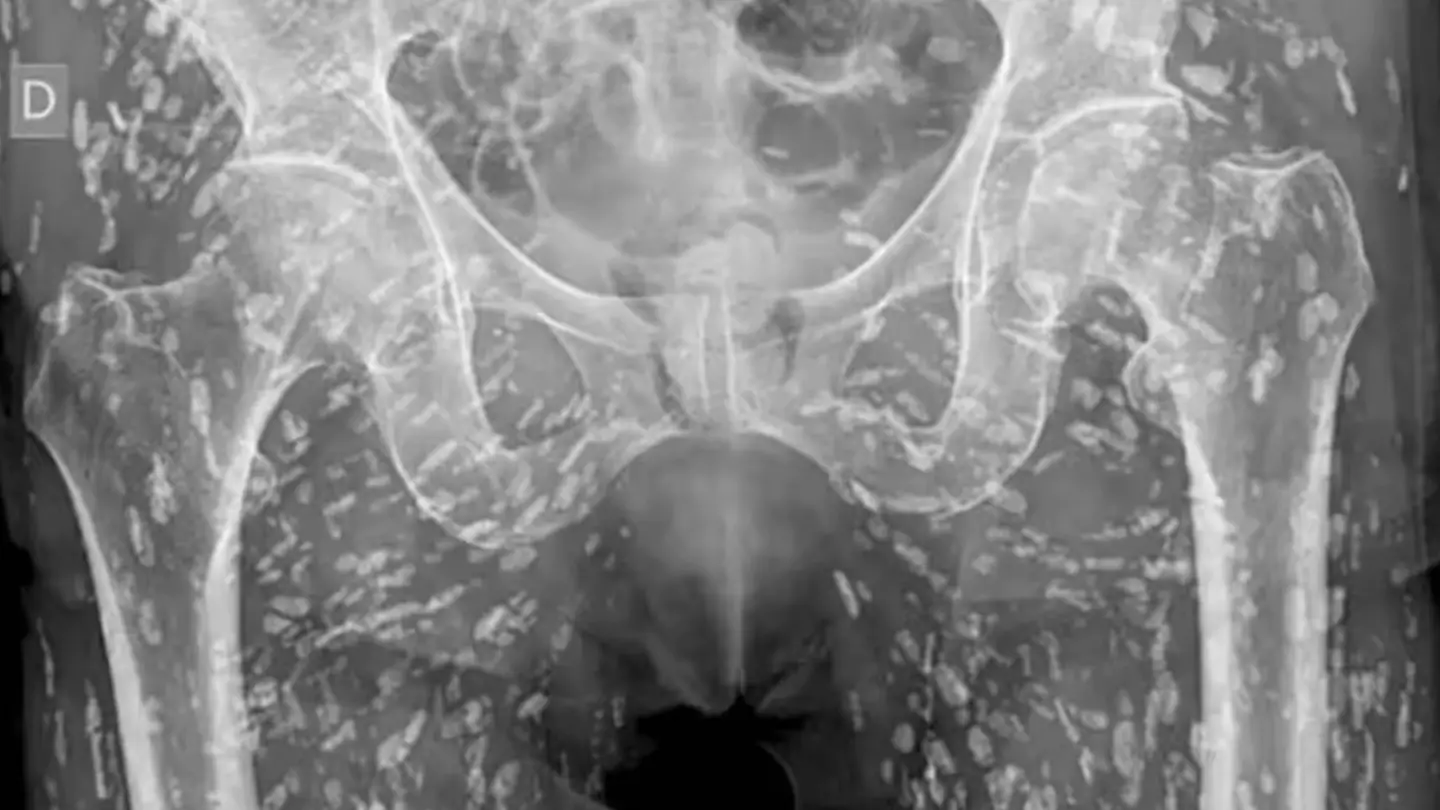

A disturbing X-ray has been shared on social media, showing what a body infested with tapeworms looks like.

Sam Ghali, of the University of Florida, uploaded the photo on X, calling it one of the 'most insane X-rays I’ve ever seen'.

"These cysts can travel anywhere throughout the entire body, heavily to the muscular and soft tissue of the hips and the legs," Ghali said.

"If just in the pelvis, they don’t pose a life-threatening problem.